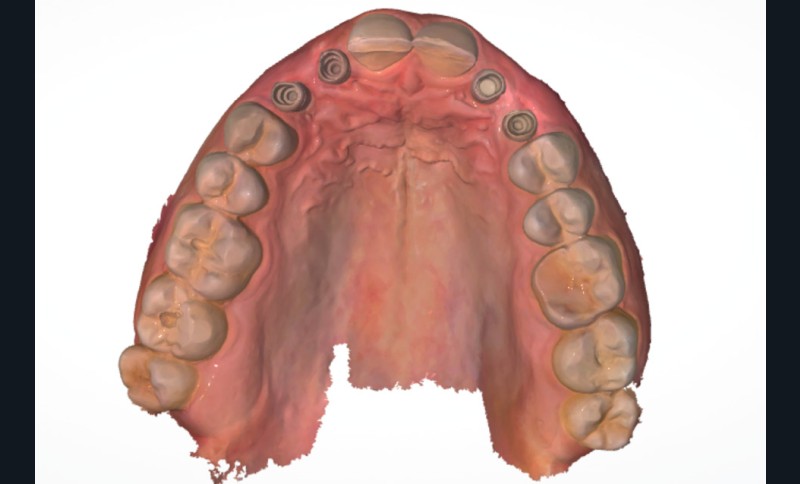

Un homme de 38 ans se présente en consultation d’implantologie pour le remplacement de ses 4 dents lactéales 52 53 62 63. Il ne présente pas d’antécédents médicaux, chirurgicaux, pas d’allergie, est non-fumeur. L’analyse clinique, radiologique et préprothétique fait apparaître (fig. 1) :

- les agénésies de 12 13 22 23 46 ;

- des usures marquées des bords libres des dents lactéales ;

- une égression compensatrice de certaines dents antérieures mandibulaires ;

- un parodonte sain et épais.

- réalisation de l’empreinte optique pour enregistrer la position implantaire (Scanbody IOFlO) (fig. 7) ;

- demande d’un wax-up numérique pour validation par le patient (fig. 8) ;